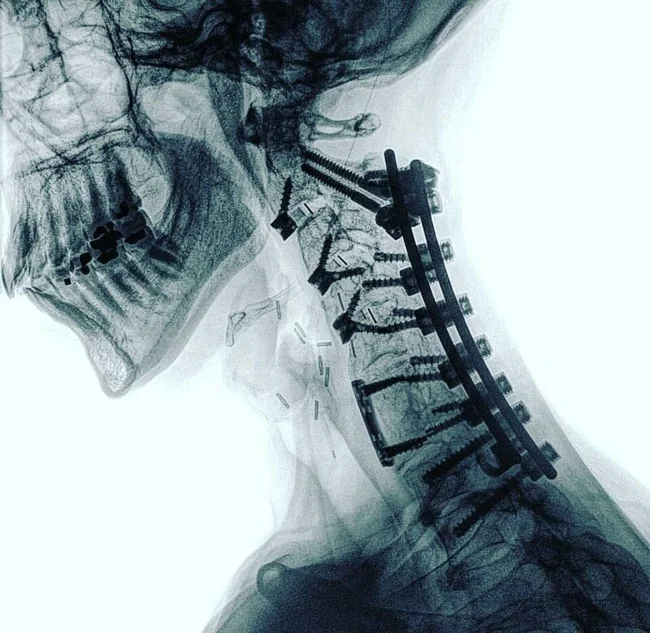

Хірургічне відновлення шийного відділу хребта